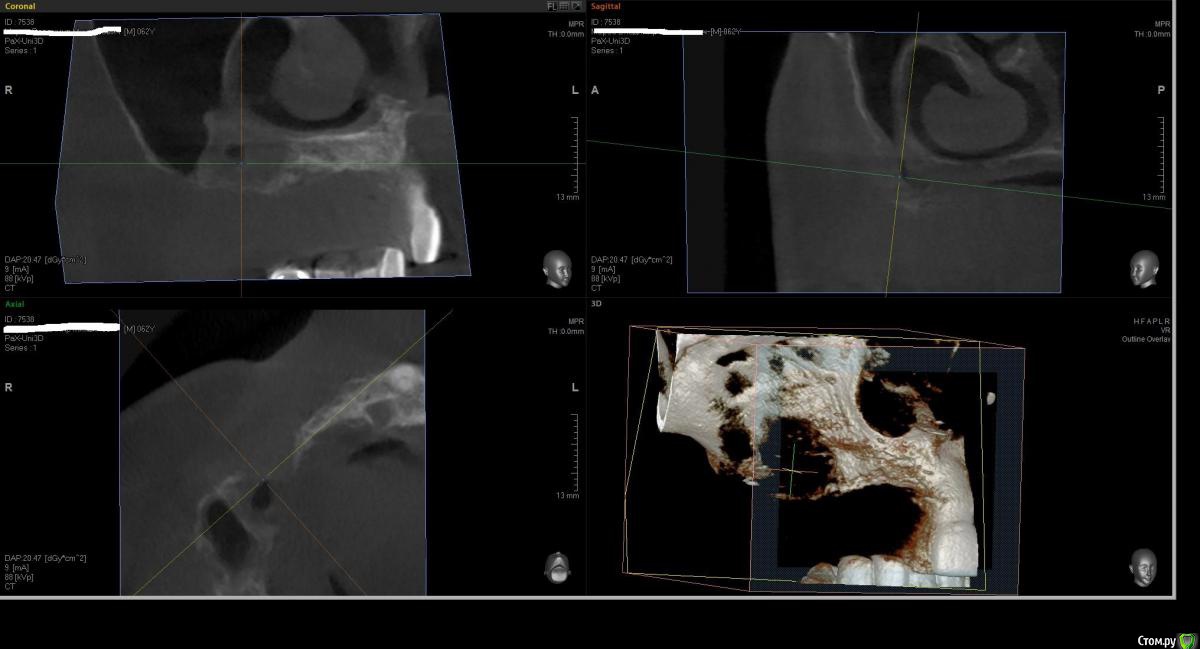

Kostoprav Опубликовано 1 августа, 2016 Поделиться Опубликовано 1 августа, 2016 что бы вы сделали в данной ситуации уважаемые коллеги? был синус и титановая сетка во фронте но увы все прокисло ((( 1 Ссылка на комментарий

Kostoprav Опубликовано 2 августа, 2016 Автор Поделиться Опубликовано 2 августа, 2016 Всё вычистить, подождать заживление и повторить.это кт уже после чистки, а повторить снова титановой сеткой?думаю снова сетка здесь не прокатит( Ссылка на комментарий

Kostoprav Опубликовано 3 августа, 2016 Автор Поделиться Опубликовано 3 августа, 2016 скисло через 3 мес, до этого все было идеально!но меня больше беспокоит вопрос что теперь с этим делать, там теперь кости особенно во фронте почти нет.какую технику использовать? Ссылка на комментарий

Kostoprav Опубликовано 3 августа, 2016 Автор Поделиться Опубликовано 3 августа, 2016 Меня не удивляет что резорбировался графт под сеткой. Но где тут графт в пазухе? Что там было с синуслифтингомначалось все как раз из синуса. пазуха разделена перегородкой, я поднял дно только в передней камере Ссылка на комментарий

Bier Опубликовано 8 августа, 2016 Поделиться Опубликовано 8 августа, 2016 Зигомы... 1 Ссылка на комментарий

kriokov Опубликовано 9 августа, 2016 Поделиться Опубликовано 9 августа, 2016 Зигомы...х\з , там по их по две с каждой стороны надо, если только на зигомах ( фо фронте с костью жиденько)но если опыт работы с ними есть - то вариант Ссылка на комментарий

Bier Опубликовано 9 августа, 2016 Поделиться Опубликовано 9 августа, 2016 конечно по 2 зигомы с каждой стороны. На мой взгляд - вариант для этой ситуации. С фронтом ничего не делать, там базис протеза будет Ссылка на комментарий